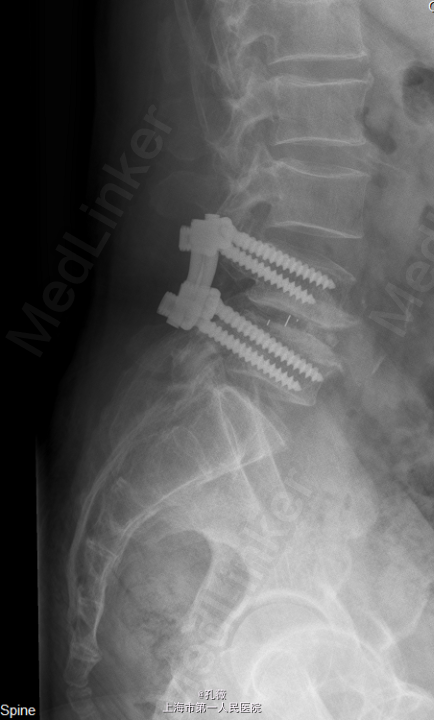

患者,男,69岁,因“腰痛伴行走活动受限10余年”入院。 患者诉40余年前有外伤致腰4椎峡部裂住院病史,后未感明显的腰部不适合疼痛。10余年前无明显诱因下出现腰痛,两侧椎旁腰骶部感觉酸胀痛,渐渐加重,行走活动受限,休息卧床时疼痛减轻,行走后加重,现患者感站立时腰痛明显,伴有右足部第1.2趾背部麻木。

脊椎外观无畸形,腰4、5棘突及双侧椎旁压痛、叩击痛(++),双下肢直腿抬高试验阴性.当地医院腰椎X线和CT提示:“腰椎退行性变,腰4椎体椎弓峡部裂伴向前滑移。”

初步诊断: 腰4椎体峡部裂,腰4椎体滑移. 处理: 行全麻下腰椎后路减压植骨融合内固定术。

术后予以补液支持治疗,密切观察患者肢体血供及感觉情况。